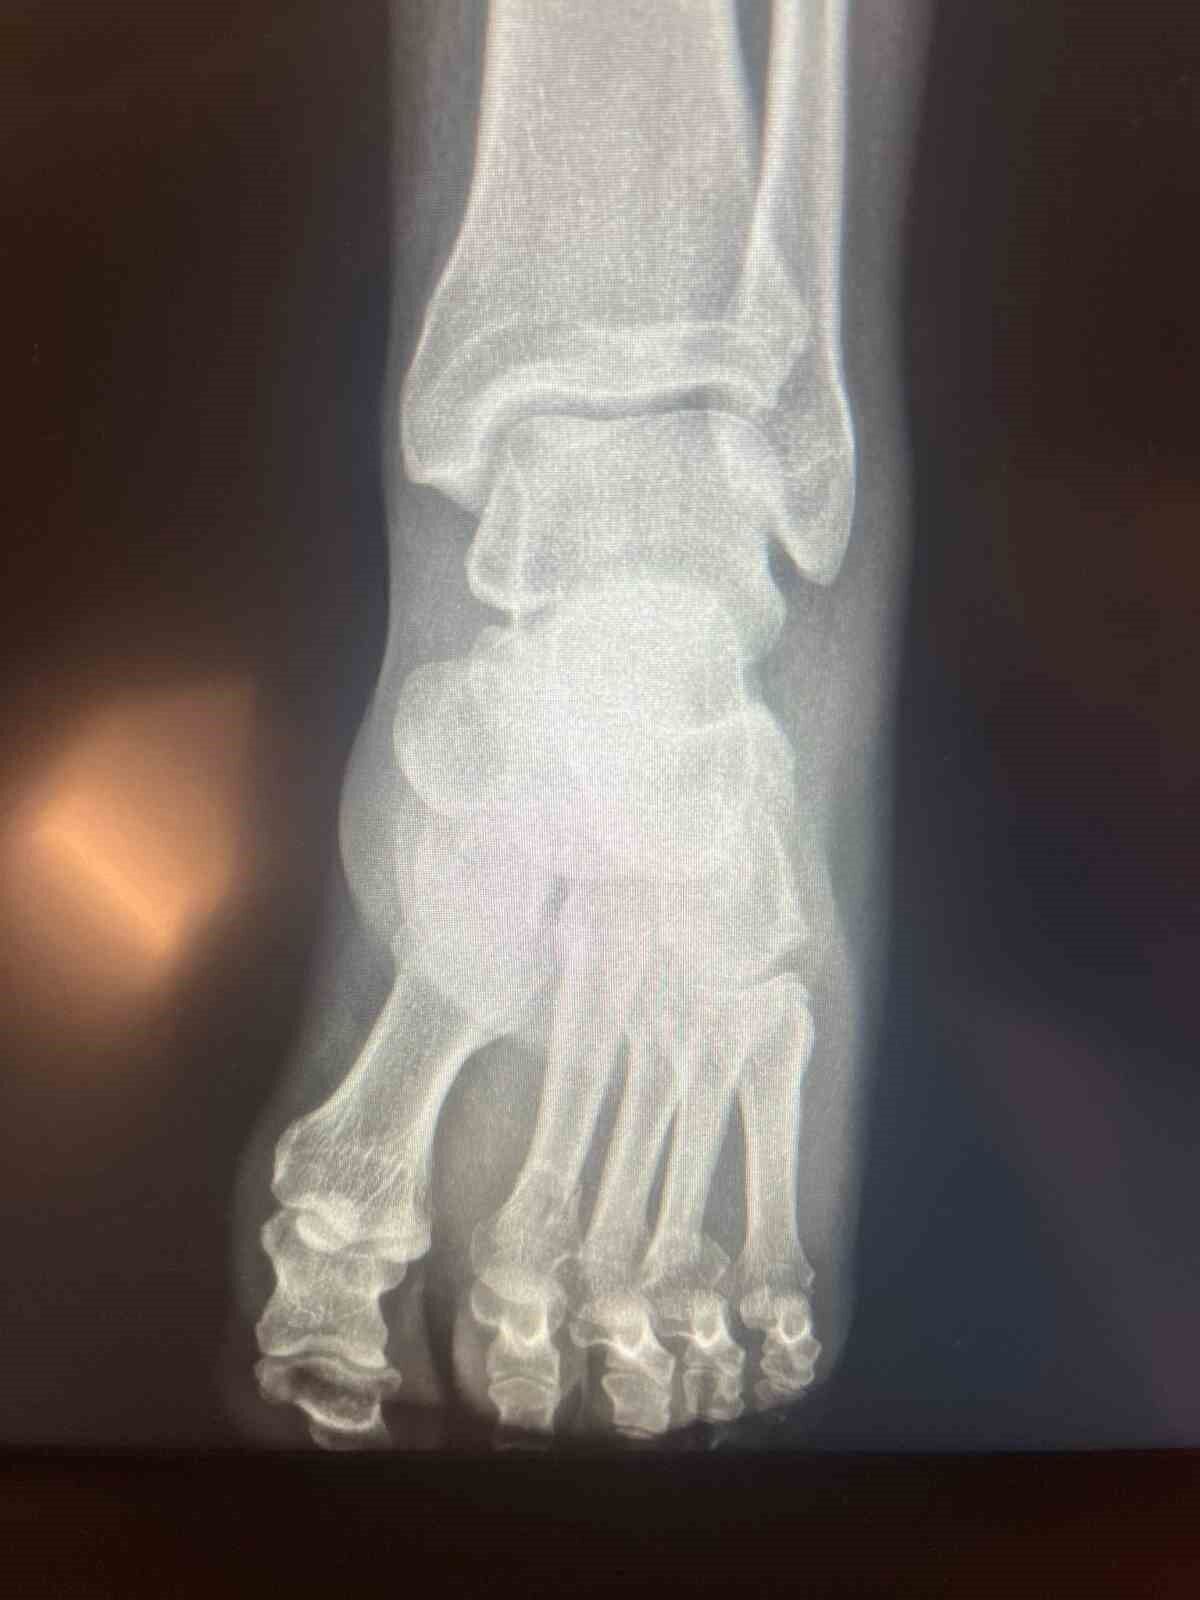

CHP Grup Başkanvekili Ali Mahir Başarır, geçen hafta TBMM’deki özel oturum öncesi gazetecilere yaptığı açıklamada, CHP Genel Başkanı Özgür Özel’in evde geçirdiği kaza sonucu ayağında ufak çaplı kırılma olduğunu duyurmuştu. Özel’in ayağında oluşan kırık hakkında sosyal medyada, Özel’in ‘ayağından vurulduğu’ iddiaları yer almıştı. Özel, tartışmalara ilişkin ayağının röntgen filmlerini paylaştı.